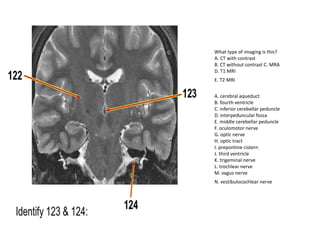

A. cerebral aqueduct

B. fourth ventricle

C. inferior cerebellar peduncle

D. interpeduncular fossa

E. middle cerebellar peduncle

F. oculomotor nerve

G. optic nerve

H. optic tract

I. prepontine cistern

J. third ventricle

K. trigeminal nerve

L. trochlear nerve

M. vagus nerve

N. vestibulocochlear nerve

What type of imaging is this?

A. CT with contrast

B. CT without contrast C. MRA

D. T1 MRI

E. T2 MRI